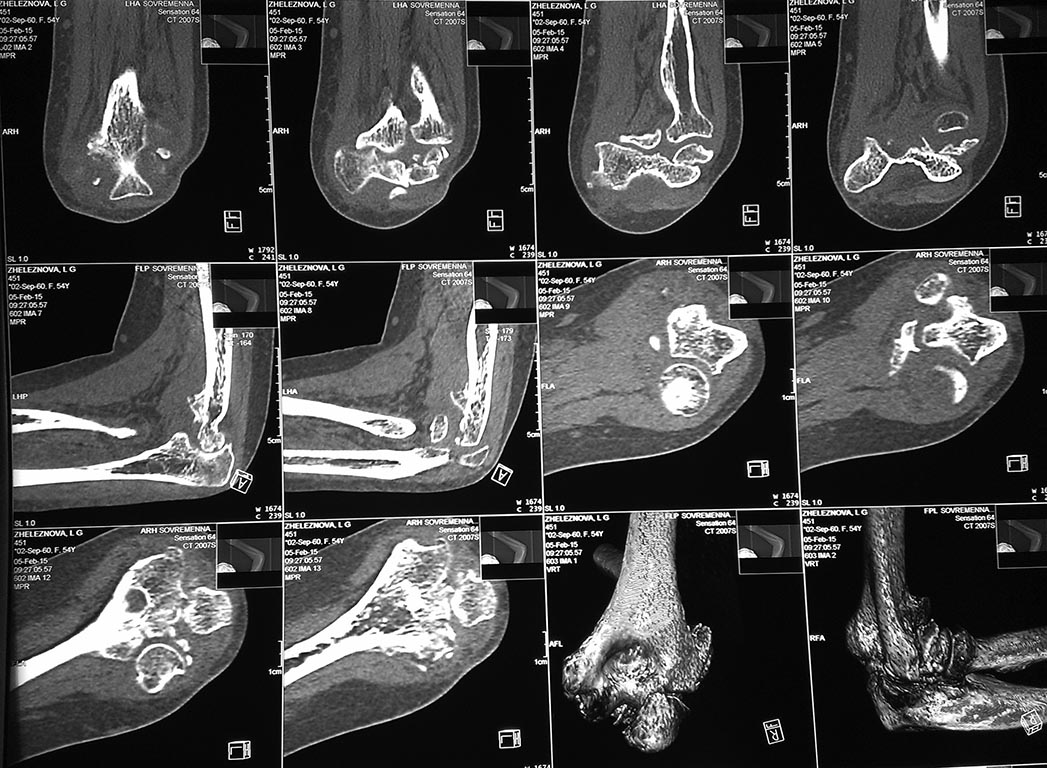

У женщины 54 лет имеются последствия закрытого вывиха костей предплечья...

Травма 08.11.14 г., окончательное вправление лишь 10.11.14 г., тогда же появились признаки нейропатии локтевого нерва, они остаются до сих пор.Движения в суставе качательные, практически анкилоз в положении 90 град.

Снимки КТ в приложении.